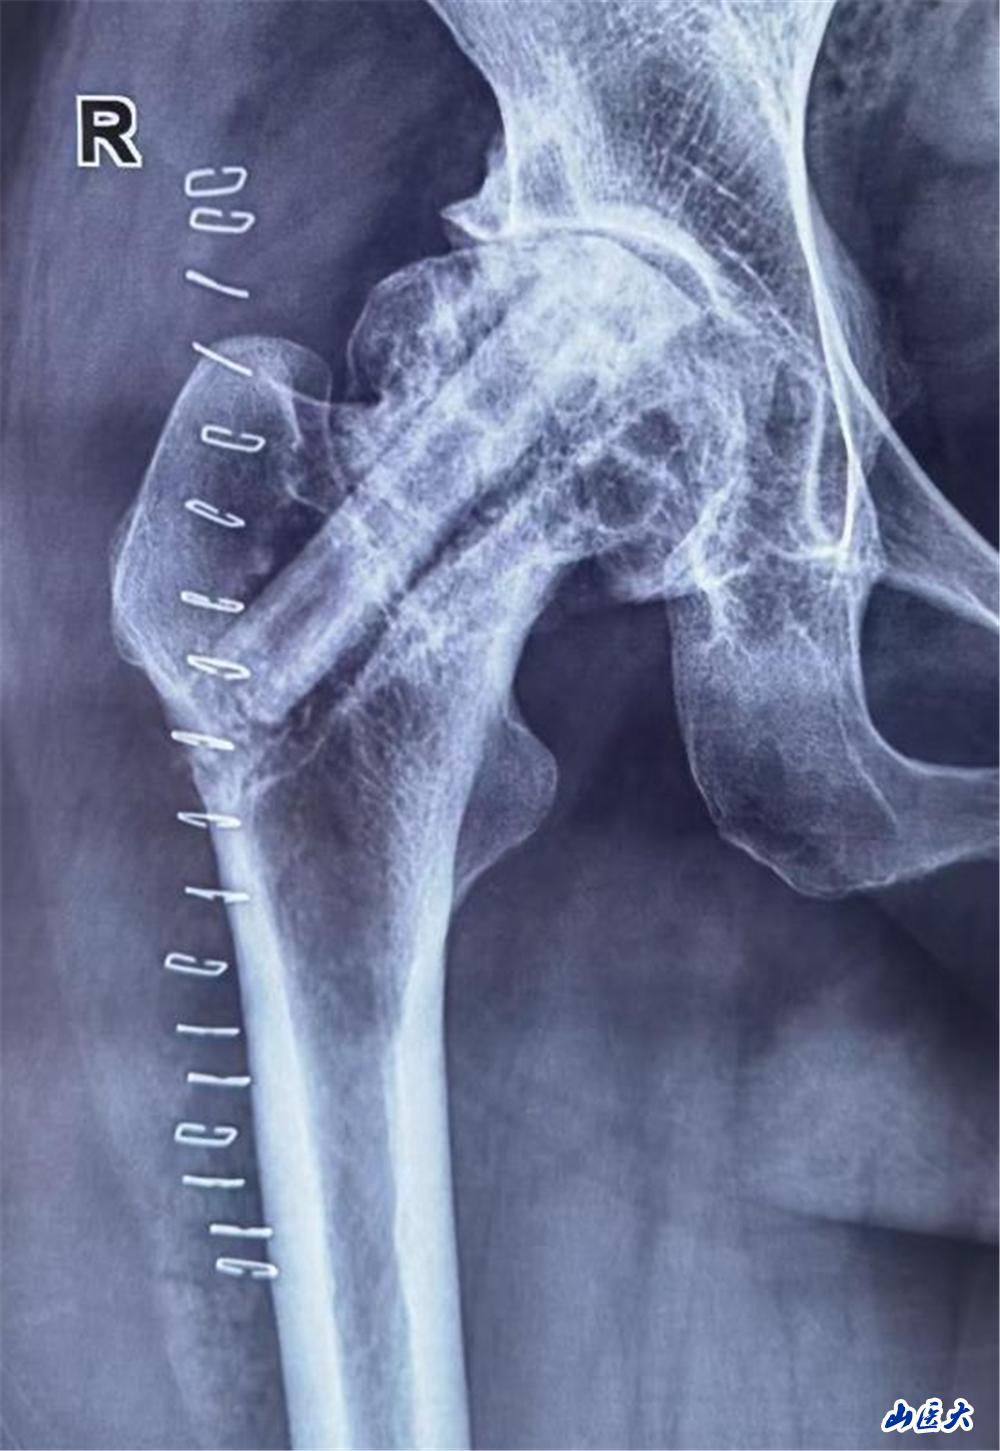

陈大姐饱受股骨头坏死折磨3年,近一个月疼痛加重,行走困难。面对患者强烈的保髋愿望,医疗团队术前通过影像学检查及血管评估,精准分析患者股骨头坏死范围及血供情况,为其量身定制了“带血管蒂的腓骨瓣移植”手术方案。这一术式能重建股骨头血运,延缓甚至避免关节置换,但对医生的显微外科技术要求极高。

手术当日面临巨大挑战,医疗团队需在患者腓骨处截取长约6cm的带血管骨瓣,并在显微镜下将细如发丝的旋髂外侧动脉与股骨头供血血管吻合。5个半小时的奋战,每一步都考验着团队的默契与技艺。

王建国凭借多年经验,精细剥离血管,避免损伤神经;团队其他手术医师在显微镜下,凝神屏息,以比头发丝还细的缝合线完成血管吻合,确保血流通畅。在大家的密切配合下,手术取得了圆满成功。